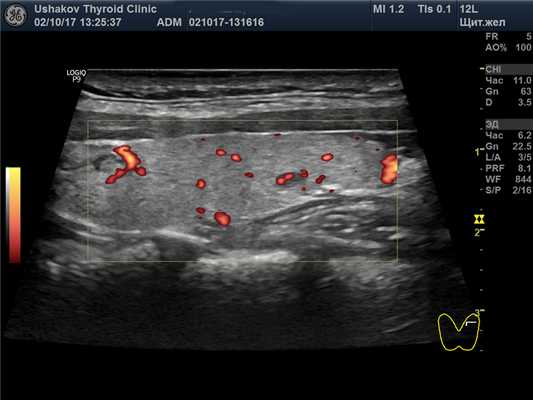

(Справа) Энергетическая допплерография, поперечная проекция: определяется диффузное повышение васкуляризации железы, часто описываемое как «тиреоидный пожар» при болезни Грейвса. При спектральной допплерографии (изображения не показаны) в сосудах обнаруживается повышение скорости кровотока в отличие от тиреоидита Хашимото (скорость не изменена). (Слева) КТ глазниц, корональная реформатированная проекция: определяется распространенная гипертрофия экстраокулярных мышц, сопоставимая с офтальмопатией Грейвса.

(Справа) Энергетическая допплерография, продольная проекция: определяется «тиреоидный пожар». При выраженной васкуляризации железы для оценки кровотока и уменьшения выраженности артефактов можно использовать высокую частоту повторения импульсов и фильтры.

о Цветовая допплерография: выраженная диффузная гиперваскуляризация паренхимы, «тиреоидный пожар»